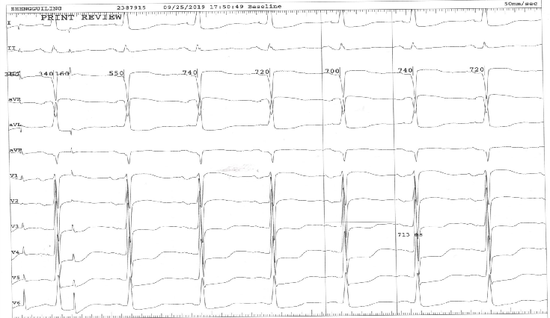

该患者动态心电图示:

心腔内电生理检查示:起搏前窦性周期时限:713ms

心腔内电生理检查示:窦房结恢复时间:784ms;校正的窦房结恢复时间:71ms(<525ms )

以上检查均显示该患者的窦房结及房室结功能正常,而窦性停搏的出现是在快速房性心律失常下导致窦房结功能一过性障碍,其存在的快速型心房颤动才是疾病的根本原因,因此确诊了快-慢综合征后,最佳治疗方案就是行房颤射频消融手术,而非安置起搏器治疗。将其房颤心律纠正为窦性心律,房颤长间歇就会消失,房颤得到根治,避免房颤卒中的并发症。肖大夫擅长心律失常介入治疗,手术过程非常顺利,术后心电图恢复为窦性心律。